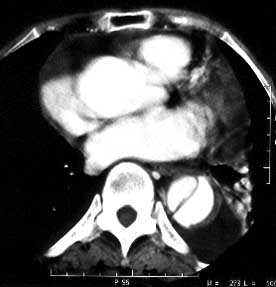

女性,71岁,胸骨后疼痛两小时来诊。体检:心界左下扩大,心率70次/每分,律齐,无杂音。x线胸片示:纵隔增宽。

ct平扫:降主动脉全程约18cm范围内管腔扩张,管腔被条索影分隔成前内、外后两腔,条索影与管壁连接处见散在点状钙化影。

增强扫描:见前内腔较小,与主动脉弓同步强化;后外腔较大,造影剂消退时间教主动脉弓延长,切管壁不均匀增厚,强化不明显。

ct诊断:降主动脉夹层动脉瘤,伴附壁血栓形成。